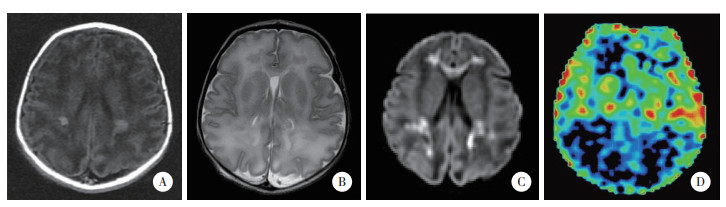

2 结果 2.1 3组ASL磁共振灌注成像检查结果所有患儿均获得满意图像。结果显示,轻度组中5例rCBF图像无显著变化,8例脑白质区灌注信号强度增高,见图 1。中度组中7例rCBF图像无显著变化,18例脑白质区灌注信号强度增高,11例脑灰质区灌注信号强度增高,14例基底节区和丘脑区灌注信号强度增高,见图 2。重度组中4例脑白质区灌注信号强度增高,3例脑灰质区灌注信号强度增高,2例基底节区灌注信号强度增高,2例丘脑内灌注信号强度增高,见图 3。

| A~C,常规MRI,双侧侧脑室后角旁可见点片状短T1短T2信号影,弥散加权呈高信号;D,ASL,脑白质区灌注信号强度增高. 图 1 轻度组典型病例MRI及ASL图像 |